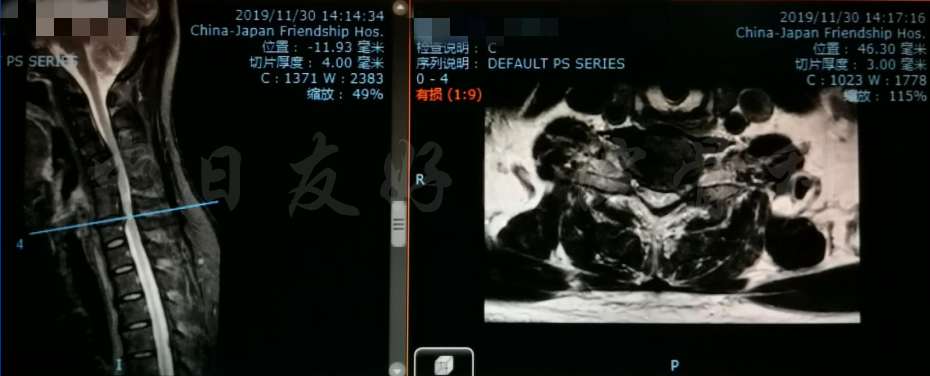

MRI

MRI颈4-5(左)、颈5-6(中)颈6-7(右)

矢状位MRI

轴位MRI:腰3-4(左)、腰4-5(中)、腰5骶1(右)

2019年11月30日 颈椎MRI提示:颈3/4颈4/5颈6/7椎间盘突出,椎管狭窄;颈5-6水平脊髓异常信号,变性可能。

颈椎MRI

颈椎MRI

颈椎各节段MRI(上下滑动)